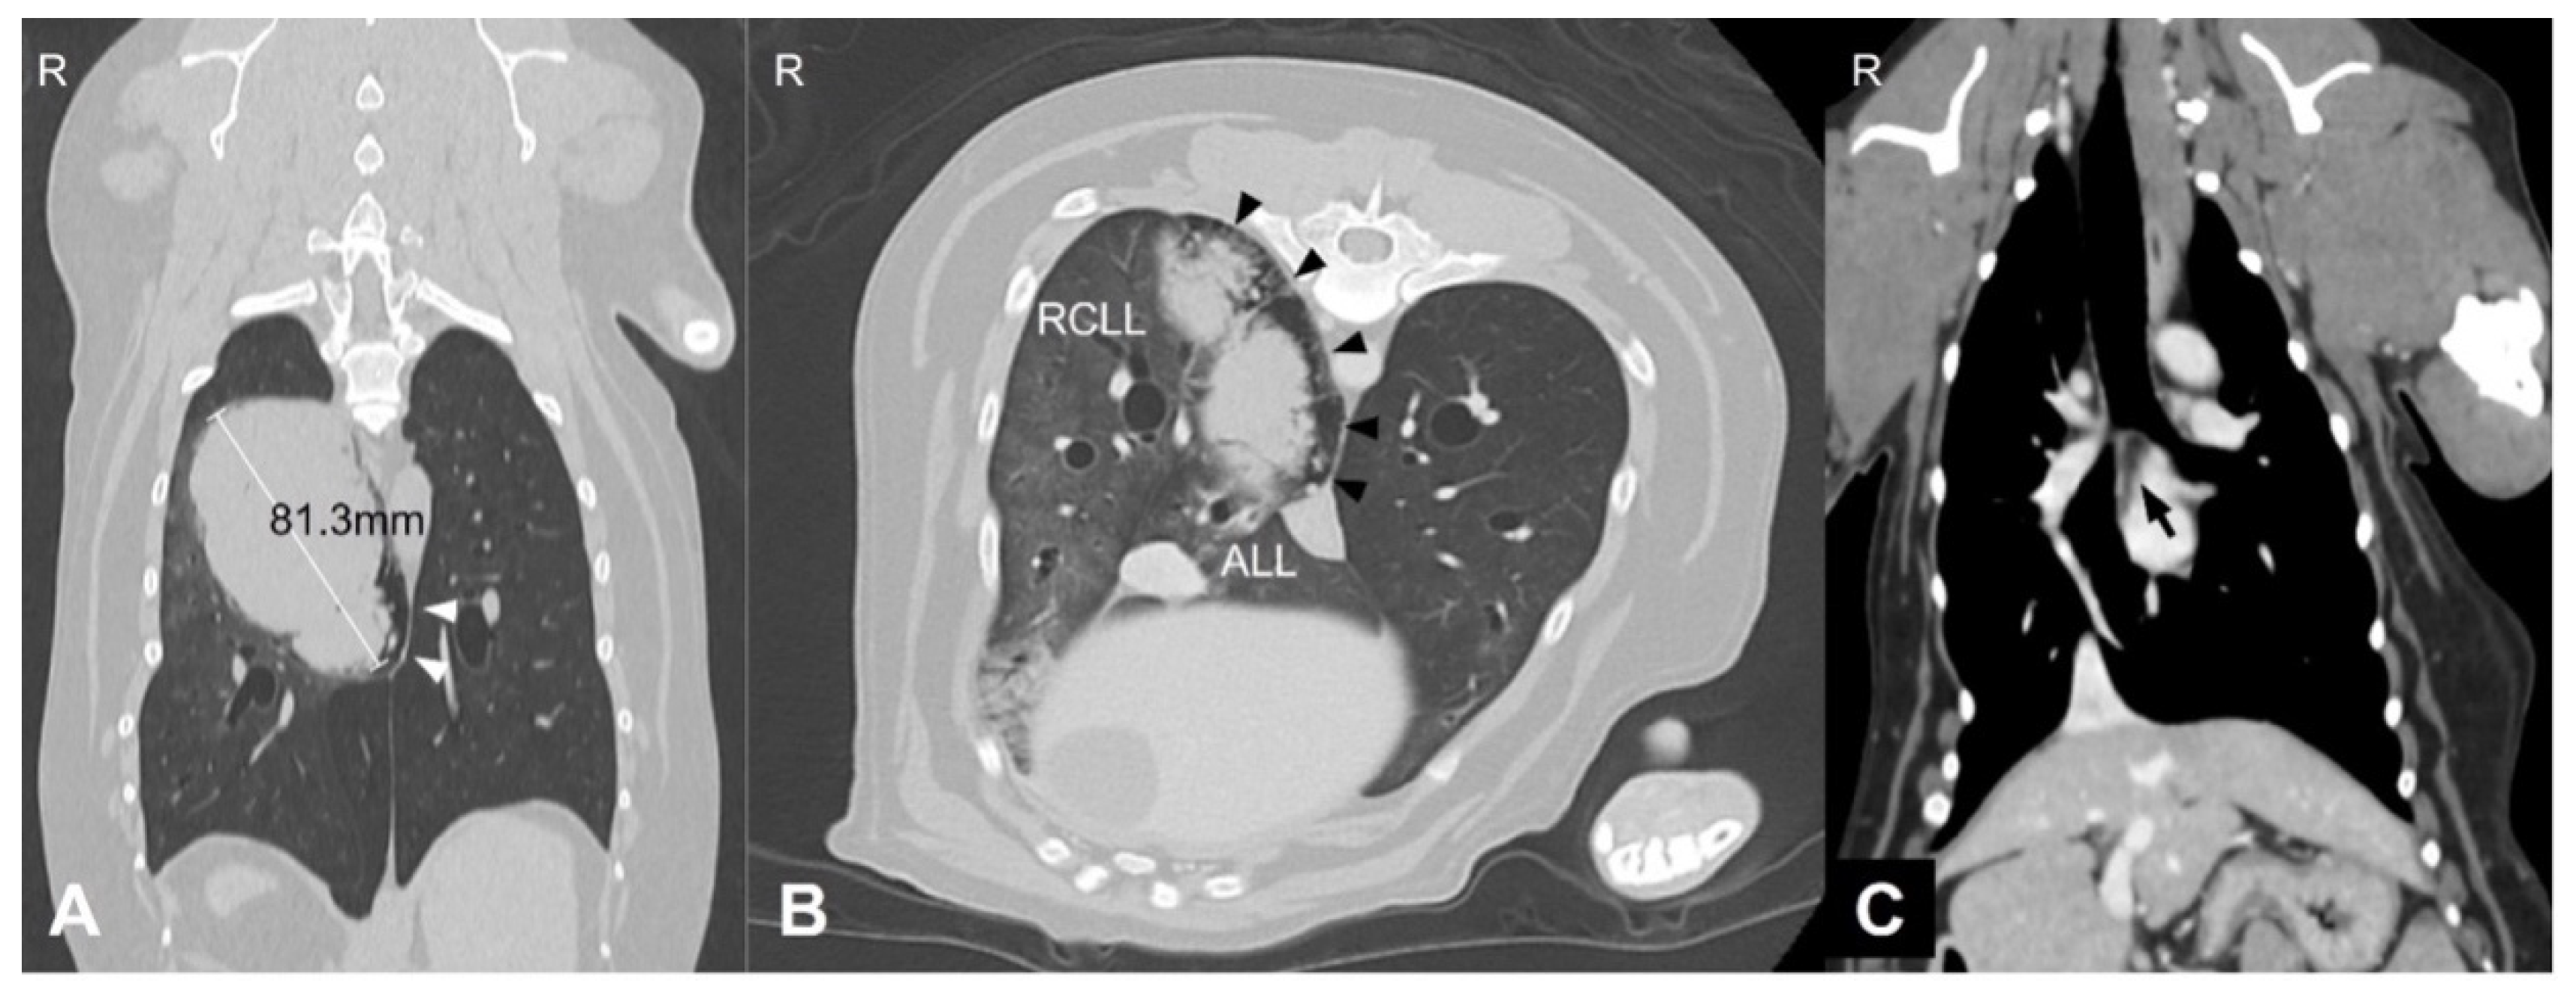

A 9-year and 8-month-old neutered male Welsh corgi weighing 13.5 kg was referred to our hospital after the incidental detection of pulmonary and splenic masses during routine health screening. At the time of presentation, the dog was clinically stable. However, the medical history included intermittent coughing, dyspnea, and cyanosis. Thoracic CT revealed an 81.3 mm pulmonary mass in the right caudal lung lobe extending into the accessory lobe. The middle tracheobronchial lymph node was enlarged and showed strong rim contrast enhancement, a CT feature commonly associated with metastatic lymph node involvement due to peripheral neoplastic infiltration and increased vascularization, making metastasis highly suspected (Figure 1). A 6.5 × 4.7 × 5.3 cm splenic mass was also identified.

Figure 1. Thoracic computed tomography (CT) images of the lung mass. (A) Transverse image showing a large soft-tissue attenuating mass (arrowhead) in the right caudal lung lobe (RCLL) with mild peritumoral emphysematous changes along the accessory lung lobe (ALL) dorsomedial margin. (B) Dorsal plane image showing the maximum diameter of the mass (arrowhead) measuring 81.3 mm. (C) Soft-tissue window image showing enlargement of the middle tracheobronchial lymph node (arrow) located caudal to the carina. Abbreviations: RCLL, right caudal lung lobe; ALL, accessory lung lobe; R, right side.